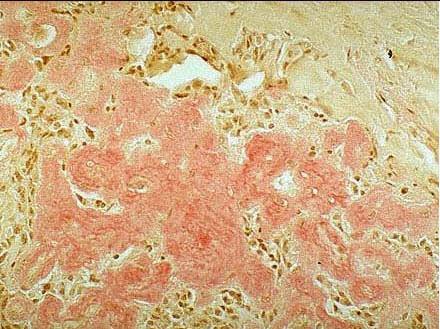

刚果红染色

阳性为红色,细胞核为蓝色。

鉴别淀粉样蛋白,可以鉴别淀粉样血管病

识别肿瘤间质中是否是淀粉样物质沉积,如甲状腺髓样癌、浆细胞骨髓瘤等